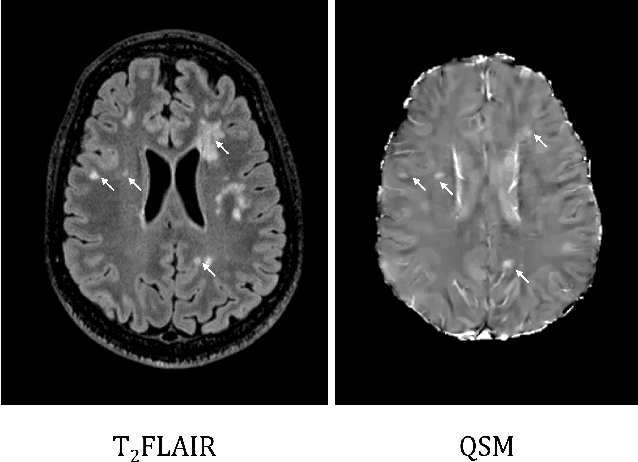

Abstract:Quantitative susceptibility maps from magnetic resonance images can provide both prognostic and diagnostic information in multiple sclerosis, a neurodegenerative disease characterized by the formation of lesions in white matter brain tissue. In particular, susceptibility maps provide adequate contrast to distinguish between "rim" lesions, surrounded by deposited paramagnetic iron, and "non-rim" lesion types. These paramagnetic rim lesions (PRLs) are an emerging biomarker in multiple sclerosis. Much effort has been devoted to both detection and segmentation of such lesions to monitor longitudinal change. As paramagnetic rim lesions are rare, addressing this problem requires confronting the class imbalance between rim and non-rim lesions. We produce synthetic quantitative susceptibility maps of paramagnetic rim lesions and show that inclusion of such synthetic data improves classifier performance and provide a multi-channel extension to generate accompanying contrasts and probabilistic segmentation maps. We exploit the projection capability of our trained generative network to demonstrate a novel denoising approach that allows us to train on ambiguous rim cases and substantially increase the minority class. We show that both synthetic lesion synthesis and our proposed rim lesion label denoising method best approximate the unseen rim lesion distribution and improve detection in a clinically interpretable manner. We release our code and generated data at https://github.com/agr78/PRLx-GAN upon publication.

Abstract:To develop a tissue field filtering algorithm, called maximum Spherical Mean Value (mSMV), for reducing shadow artifacts in quantitative susceptibility mapping (QSM) of the brain without requiring brain tissue erosion. Residual background field is a major source of shadow artifacts in QSM. The mSMV algorithm filters large field values near the border, where the maximum value of the harmonic background field is located. The effectiveness of mSMV for artifact removal was evaluated by comparing with existing QSM algorithms in a simulated numerical brain, 11 healthy volunteers, by assessing image quality in routine clinical patient study $(n=43)$, and by measuring lesion susceptibility values in multiple sclerosis patients $(n=50)$, a total of $n=93$ patients. Numerical simulation showed that mSMV reduces shadow artifacts and improves QSM accuracy. Better shadow reduction, as demonstrated by lower QSM variation in the gray matter and higher QSM image quality score, was also observed in healthy subjects and in patients with hemorrhages, stroke and multiple sclerosis. The mSMV algorithm allows reconstruction of QSMs that are equivalent to those obtained using SMV-filtered dipole inversion without eroding the volume of interest.